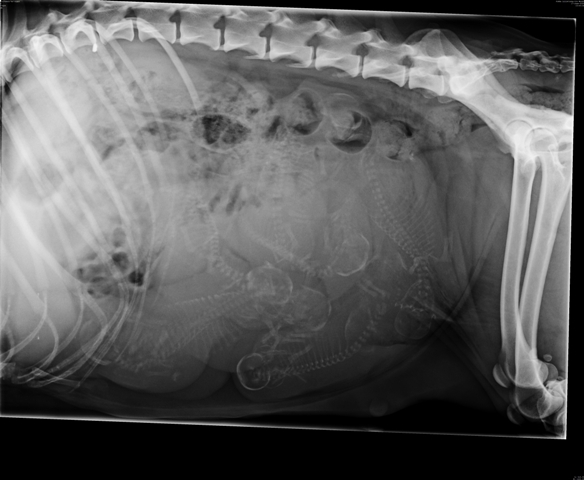

17.6. käytiin penturöntgenissä.

8 pentua sielä eläinlääkärin mukaan olisi tulollaan